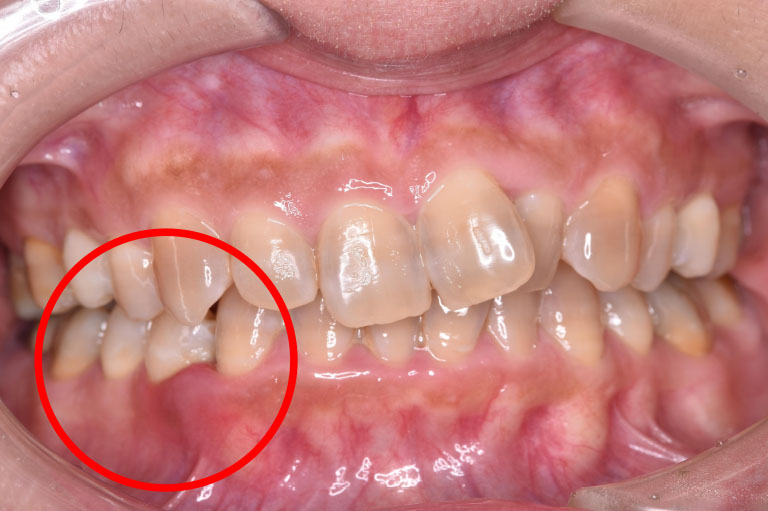

case.1

治療前

治療後

| 治療名 | 歯周組織再生療法 |

| 患者様情報 | 50代 女性 |

| 担当医 | 亀岡 聡貴 先生 |

| 費用 | 15.000円 (税込) 保険内 |

| 主訴 | 右下3番付近の歯茎が 1週間前から腫れている。 |

| 治療期間 | 1年 |

| 治療内容 | 歯周基本治療(SRP、TBI、咬合調整など)+歯周外科治療(再生療法)を行いました。全顎的に歯茎の炎症も落ち着き、レントゲン上でも骨の再生を認められました。 |

| 治療のリスク | 現在の状態の維持のため、継続的にメインテナンスを行う必要があります。 |